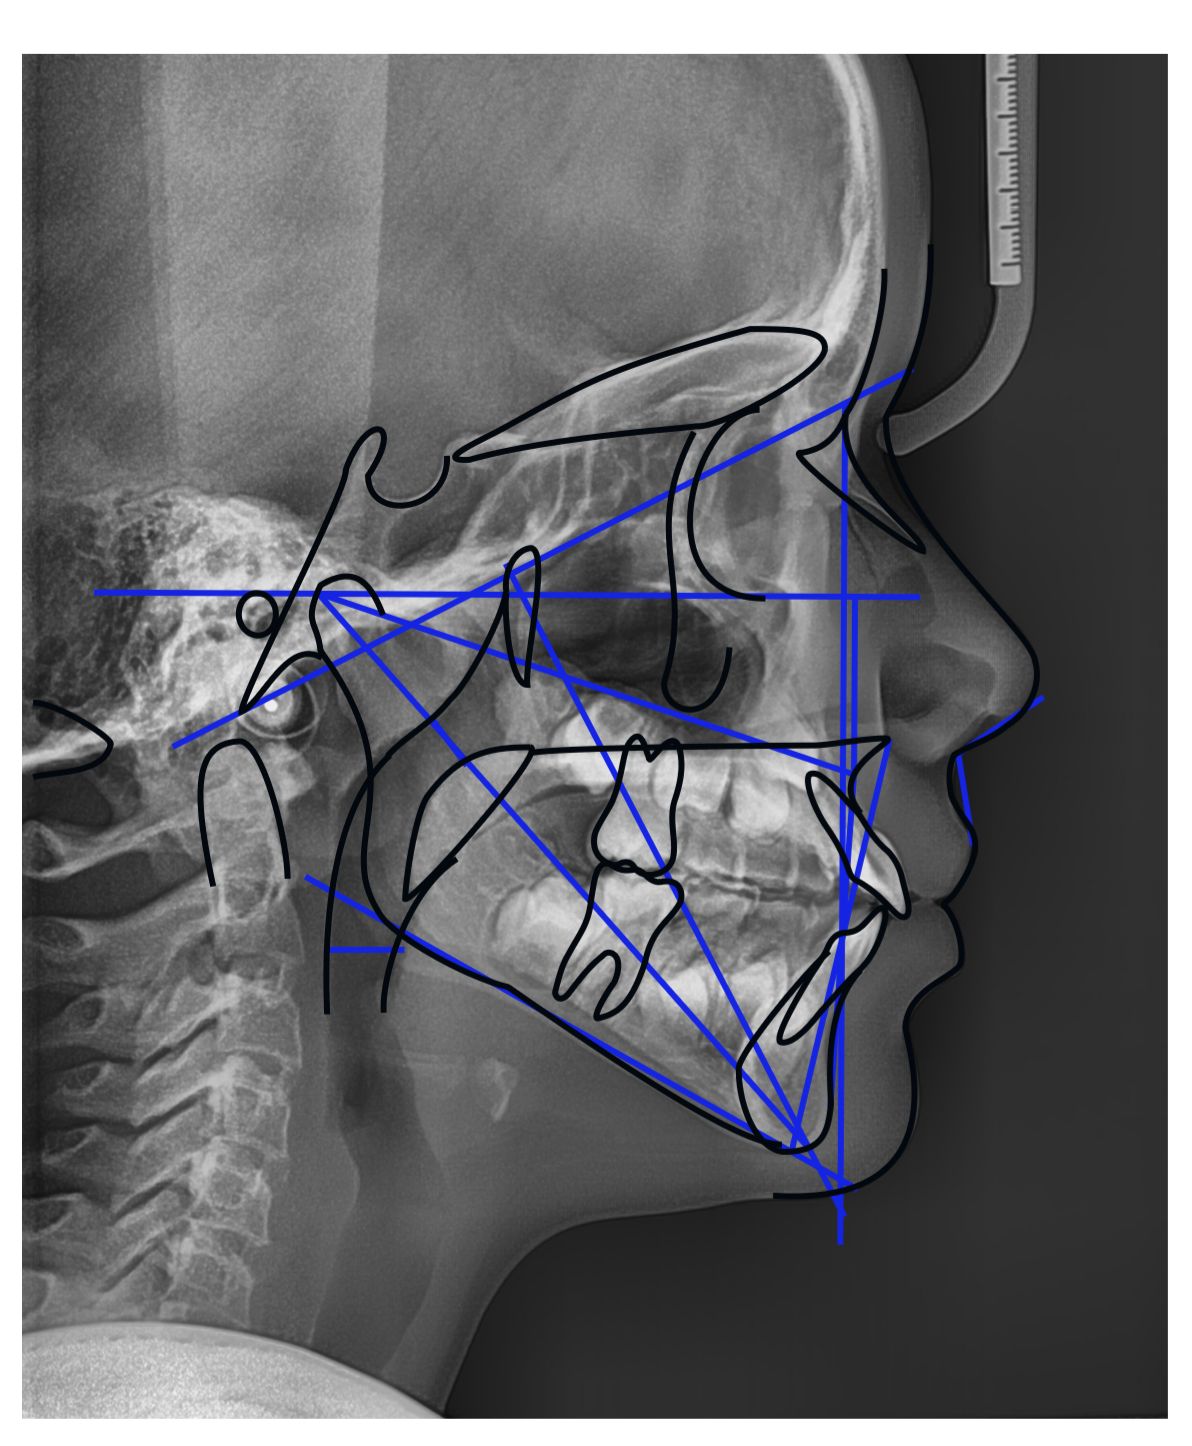

Telerradiografia

Imagem lateral do crânio. Muito usada em tratamentos ortodônticos.

Documentação Ortodôntica

Conjunto de exames e fotos para planejar o aparelho ortodôntico com segurança e precisão.